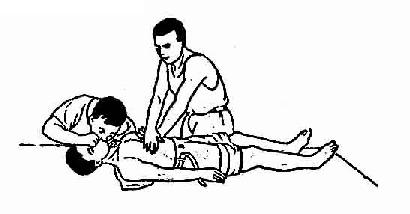

5.按压与通气的协调

(1)一人操作 现场只有一个抢救,吹气与按压之比为2:15,即连续吹气2次,按压15次,两次吹气间不必等第一口气完全呼出。2次吹气的总时间应在4-5秒之内。

(2)两人操作 负责按压者位于病人一侧胸旁,另一人位于同侧病人头旁,负责疏通气管和吹气,同时也负责监测颈动脉搏动。吹气与按压之比为1:5(图20-3,为避免术者疲劳二人工作可互换,调换应在完成一组5:1的按压吹气后间隙中进行。在按压过程中可暂停按压以核实病人是否恢复自主心搏。但核实过程和术者调换所用时间,均不应使按压中断5秒以上。

胸外心脏按压与口对口人工呼吸(二人操作)